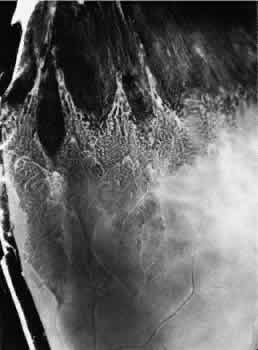

Fig. 11. Partially enclosed ora bay in a 20-year-old woman. Posteriorly, the ora bay extends 1.8 mm behind general line of ora serrata, and the retina shows a large area of typical cystoid degeneration. Anteriorly, the ora bay is embraced by two long dentate processes that converge toward, but do not meet, a prominent ciliary process of the pars plicata. (× 12.)